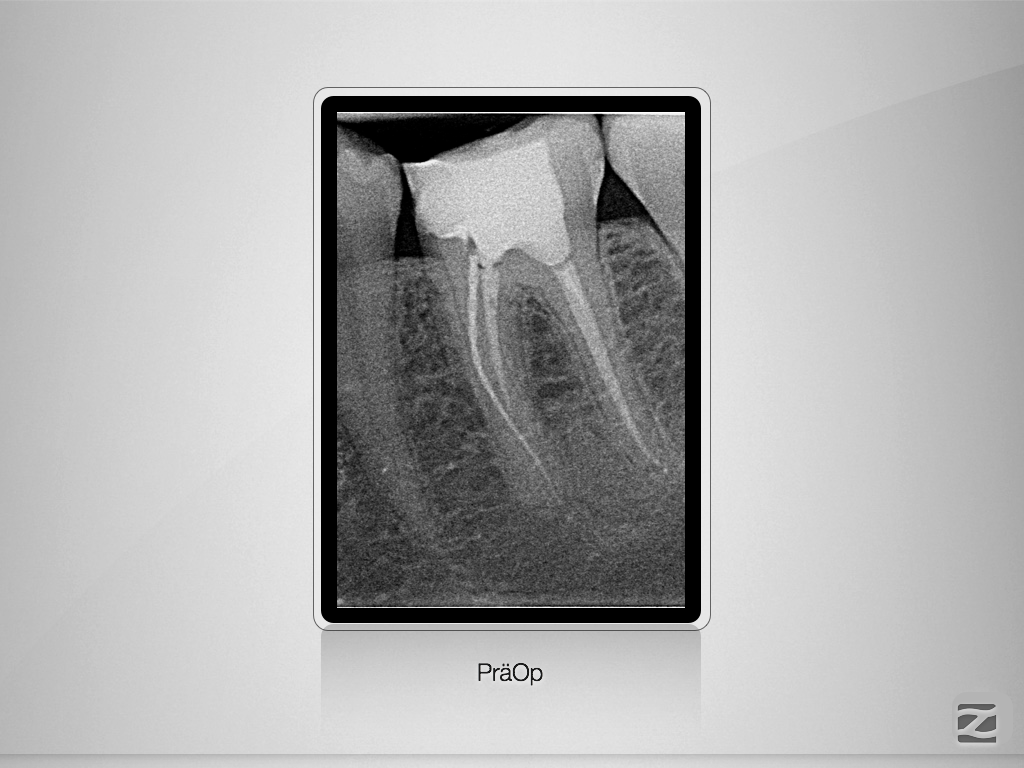

Fraktur auf voller Arbeitslänge